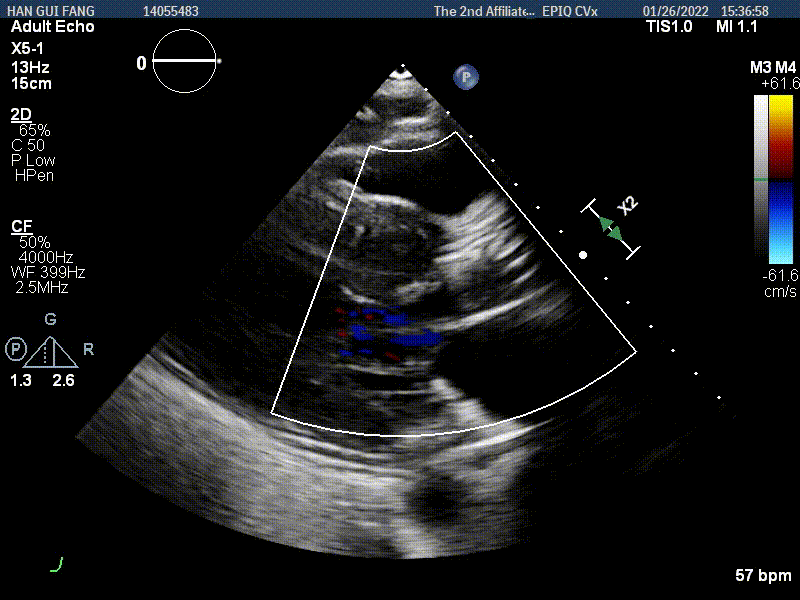

手术使用Z-Med 20mm球囊预扩两次,植入AV23 TaurusNXT主动脉瓣,Snare圈套器协助输送系统过弓、过瓣,120次/分起搏频率下,在左右重合位影像下释放瓣膜达到工作位,造影显示位置偏深,完全回收两次后释放达工作位,造影显示位置仍然不理想,之后第三次使用部分回收,精准释放瓣膜,之后使用Z-Med 20mm球囊后扩张两次。术后即刻超声心动图评估显示瓣膜位置良好,微量瓣周漏,主动脉瓣口峰值流速为1.90m/s,平均跨瓣压差为8mmHg,有效瓣口面积 1.60cm²,血流动力学指标理想。

超声影像